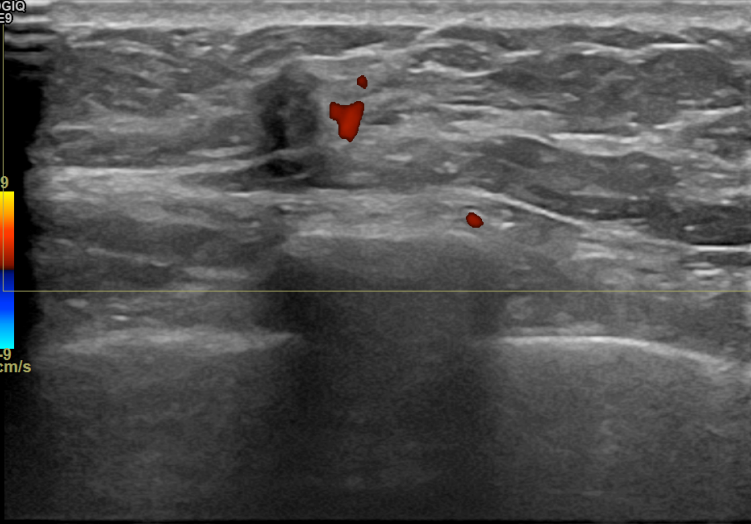

상기환자 유방추적검사위해 내원하신 50대 초반 여성분으로 의심스러운

우측혹 조직검사 시행해 침윤성암으로 진단되었습니다